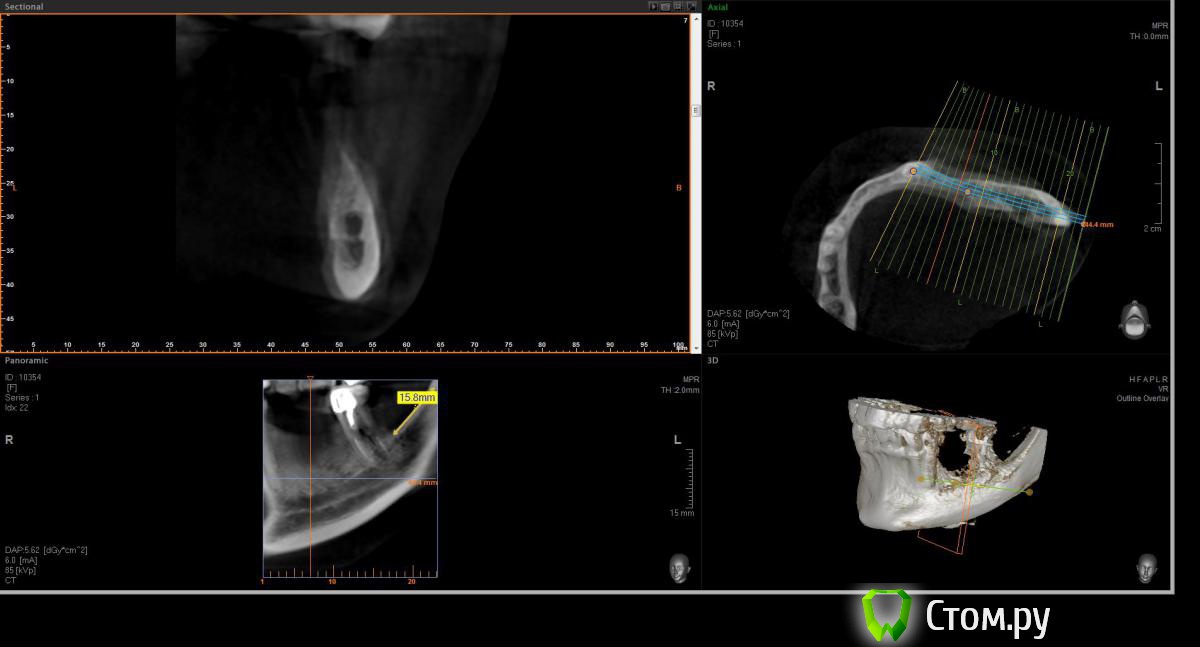

Opimar Опубликовано 21 июня, 2014 Поделиться Опубликовано 21 июня, 2014 Здравствуйте коллеги. Прошу вашей помощи и совета с пациенктой. В анамнезе травматичное удаление около 2-3 лет назад 35-36. Со слов пацинтки удалялось долотом и в 2 приема, вообщем по прошествию времени результат плачевный К мостовидному протезу пациентка не готова, очень хочет лечение с имплантантами и готова к костной пластике. Восстановить такой дефект ,если я правильно понимаю, более-менее прогнозируемо можно только с трансплантацией аутокостных блоков. Как раз по типу того как выкладывал Mane http://forum.stom.ru/topic/25799-kk-monokortikalnye-bloki/ либо по Кюри. Сам склоняюсь к забору блока с наружной косой линии или с подбородка. С блоками работать буду первый раз. Прослушал курсы Томаса Хансера. Прошу высазать идеи и предложения,возможны ли альтернативные методы? Кт прилагаю. Спасибо Ссылка на комментарий

Opimar Опубликовано 21 июня, 2014 Автор Поделиться Опубликовано 21 июня, 2014 Выкладываю еще. Пошагово от 34-37 Ссылка на комментарий

Bier Опубликовано 21 июня, 2014 Поделиться Опубликовано 21 июня, 2014 Выкладываю еще. Пошагово от 34-37темная точка достаточно высоко, это по моему не нерв, нерв ниже, я правильно понимаю? Ссылка на комментарий

Opimar Опубликовано 21 июня, 2014 Автор Поделиться Опубликовано 21 июня, 2014 темная точка достаточно высоко, это по моему не нерв, нерв ниже, я правильно понимаю?Да он ниже и язычнее. Провел от менталиса там еще запас есть. Ссылка на комментарий